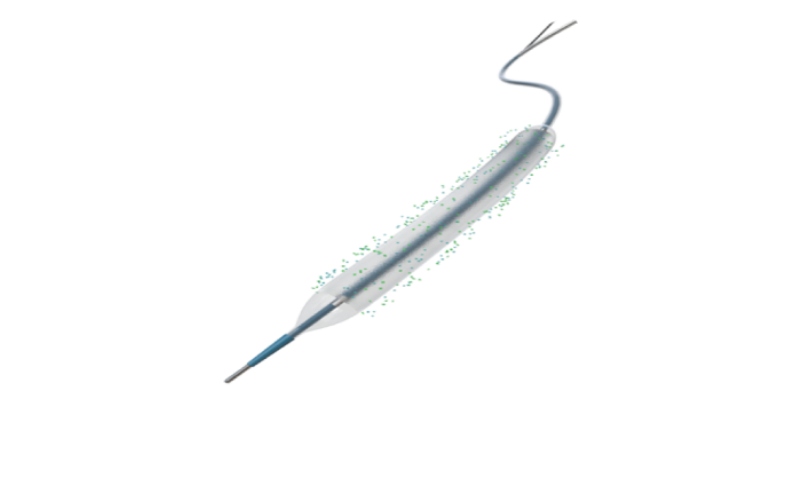

Lepu yüksek teknoloji tıbbi cihazlar ve ekipmanları

Kardiyovasküler tıbbi cihazlarda lider lepu medical, 190 iştiraki küresel bir ağa sahiptir. 214 ce sertifikalı ve 34 fda onaylı ürünle lepu, tıbbi cihazları, ilaçları, sağlık hizmetlerini ve kalp bakımı için mobil sağlık hizmetlerini kapsayan entegre bir platform kuruyor. Şirket sırasıyla 2009 ve 2022 yılında shenzhen borsası (300003) ve İsviçre borsasında listelenmiştir.